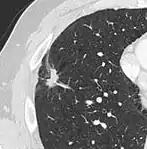

Lobulated nodule.[9]

Spiculated lung nodule.[9]